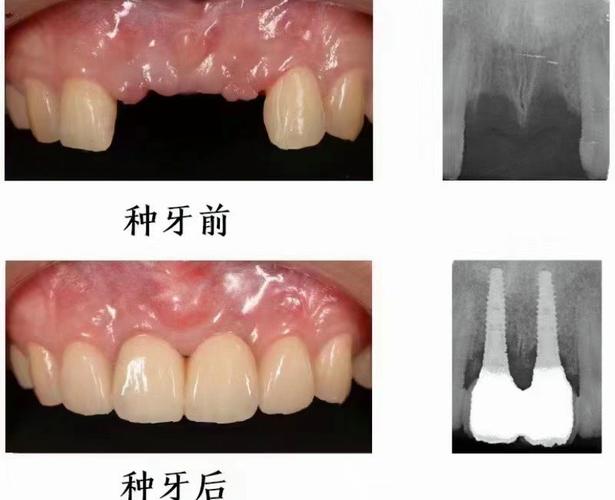

种植牙种太深是指种植体在颌骨内植入时,其平台或尖端位置超出理想解剖范围,低于牙槽嵴顶平面或侵入邻近重要结构如下颌管、上颌窦等,这一情况虽不常见,但一旦发生,可能对患者口腔健康、功能及美观造成多方面影响,需引起重视。

种植牙种太深的危害不容忽视,最直接的是对邻近解剖结构的损伤:当下颌后牙区种植体过深时,可能压迫或损伤下牙槽神经,导致下唇、颏部麻木、感觉异常,严重者可出现持续性疼痛;上颌后牙区种植体若穿透上颌窦黏膜,可能引发上颌窦炎,表现为鼻塞、流脓、面部胀痛,甚至导致种植体周围感染,种植体位置过深会影响修复效果:种植体平台低于牙槽嵴顶过多,会导致基台连接困难,修复体高度不足,影响咬合功能;牙龈组织因缺乏足够支撑可能出现萎缩,影响美观,远期来看,种植体过深还可能因周围血供差、应力集中等问题,增加种植体周围炎、骨吸收甚至种植体松动的风险。

针对种植牙种太深,处理方法需根据具体情况选择,若术中即时发现,且种植体位置偏差较小,可通过调整基台角度或使用个性化基台补救;若已侵入重要结构(如下颌管、上颌窦),需及时取出种植体,待骨愈合后重新植入,术后若出现神经损伤,可给予甲钴胺、维生素B族等营养神经药物,多数患者在3-6个月内可逐渐恢复;若合并上颌窦炎,需进行抗感染治疗,必要时行上颌窦修补术,对于修复期患者,可通过牙龈成形术、临时冠引导牙龈塑形等方式改善美观,若咬合问题严重,可能需拆除修复体重新制作。